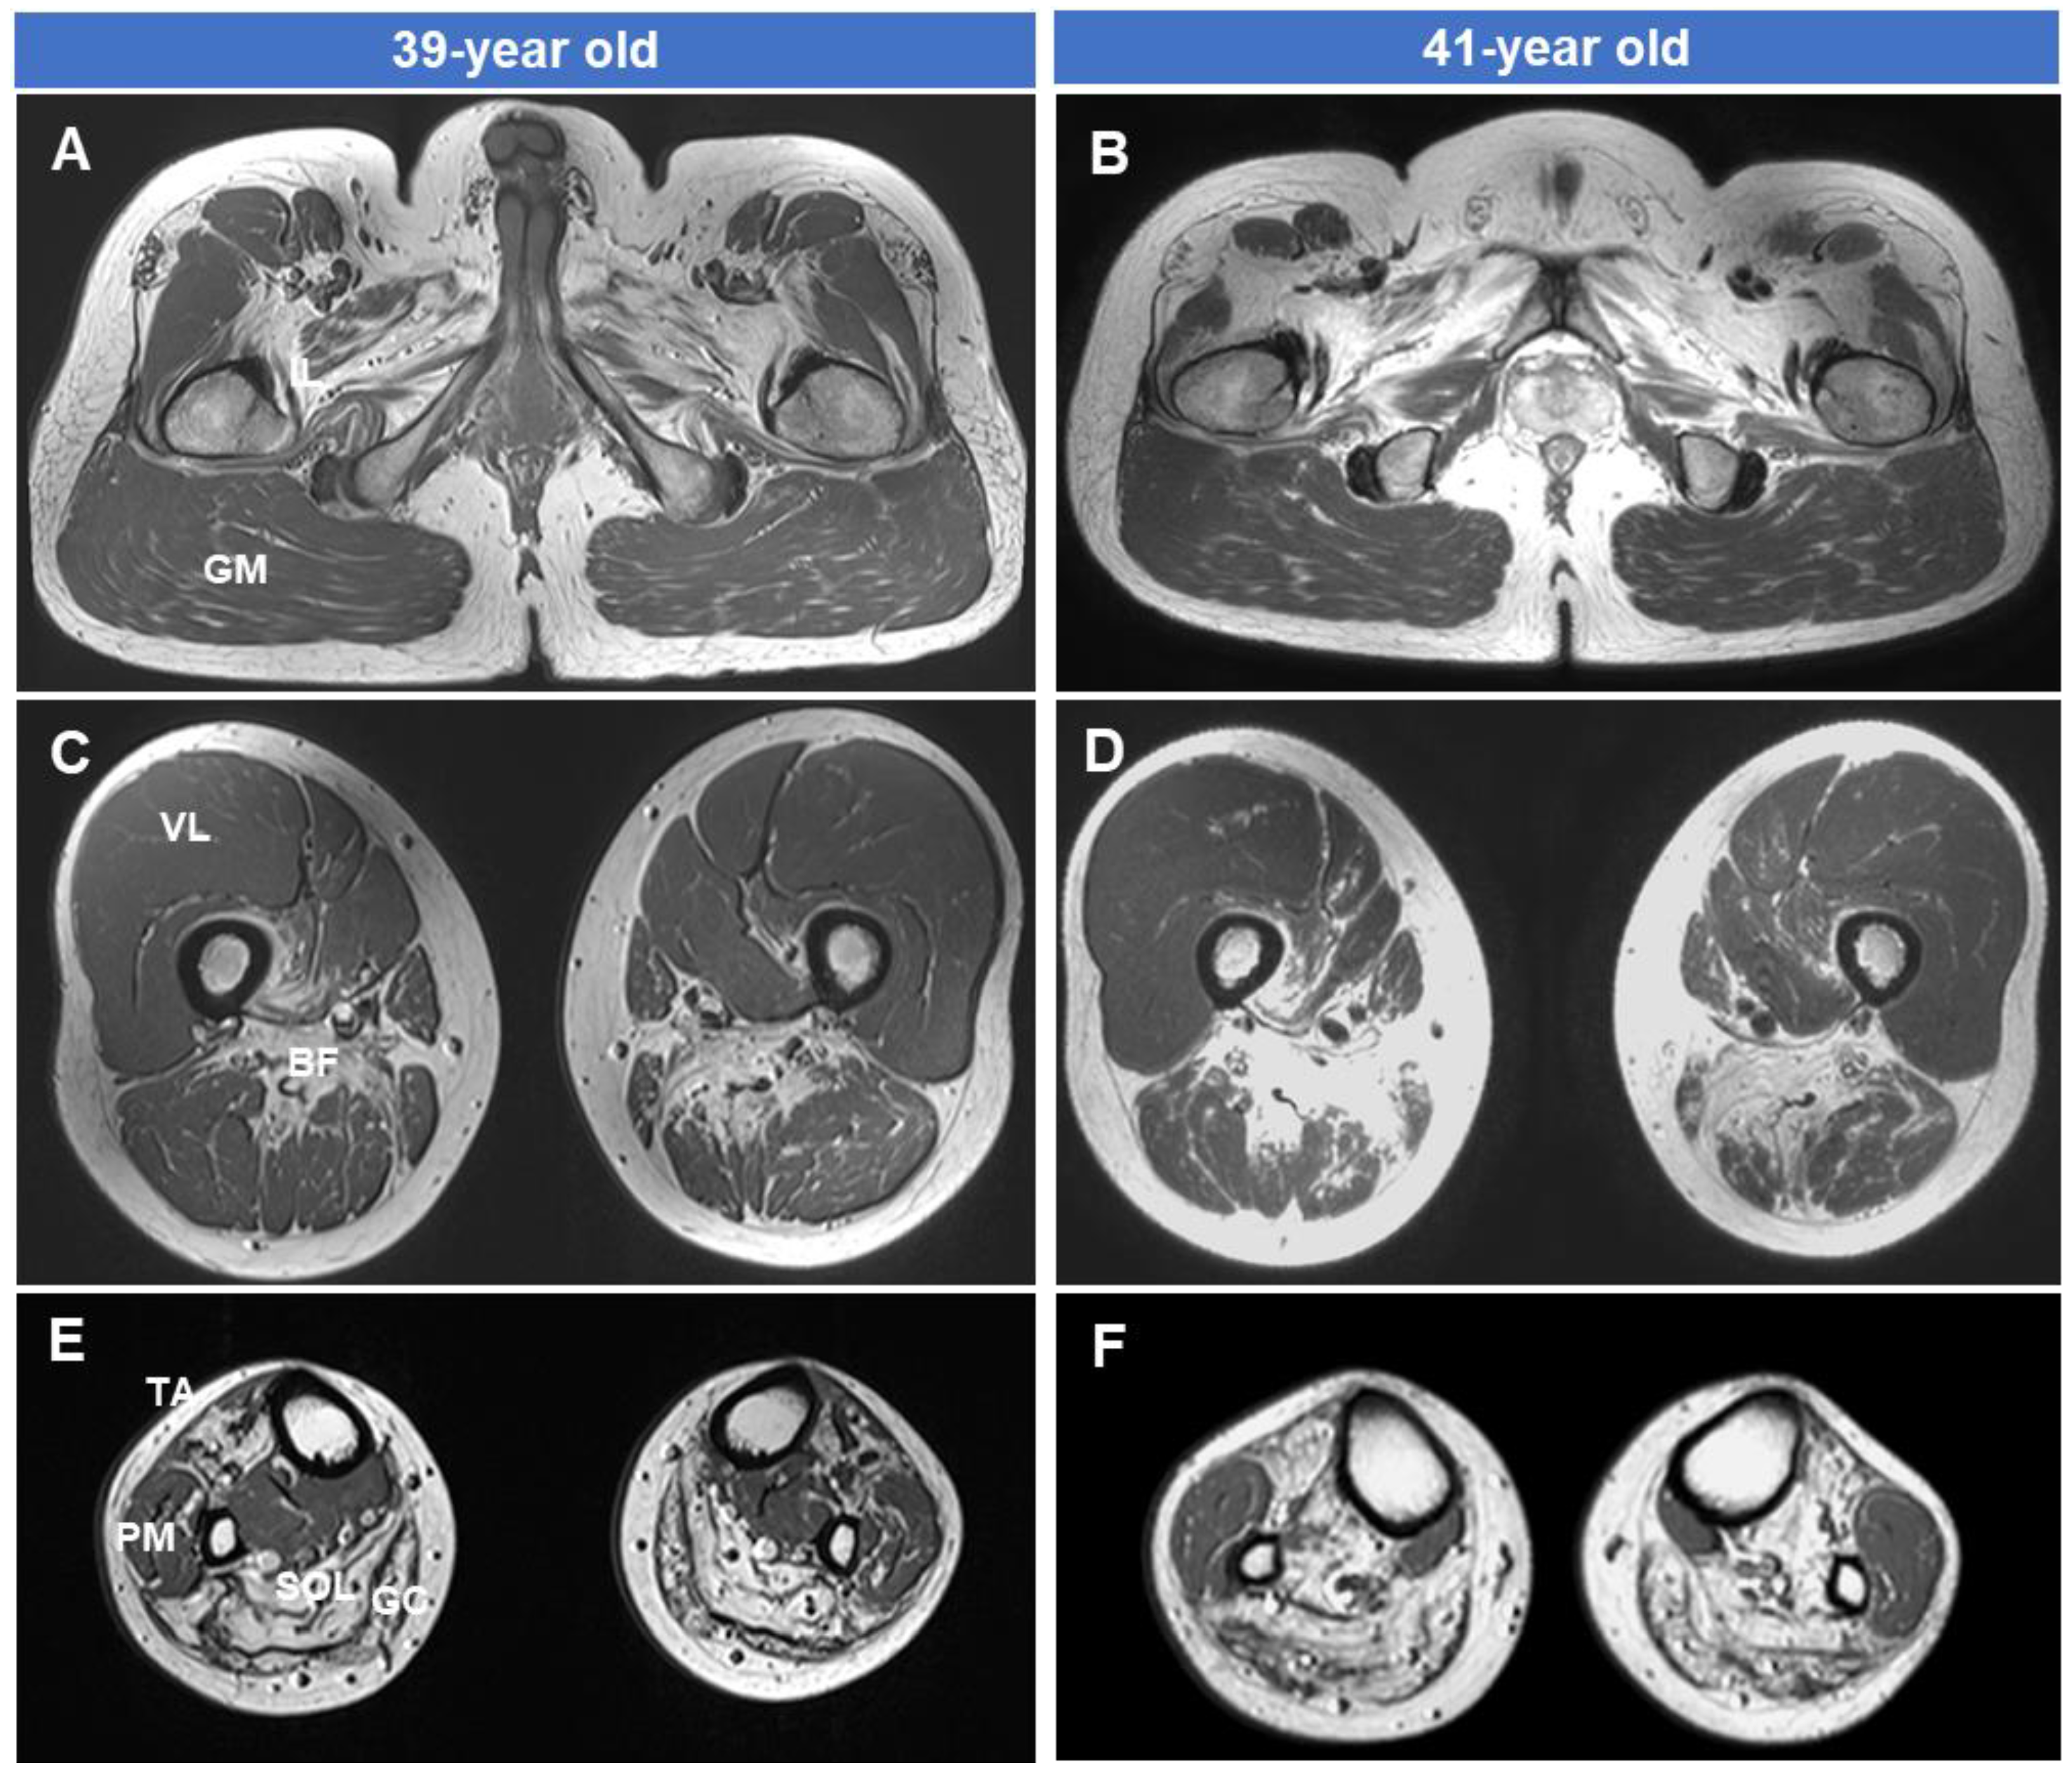

3.4. Fatty Replacements of Lower Extremity Muscles